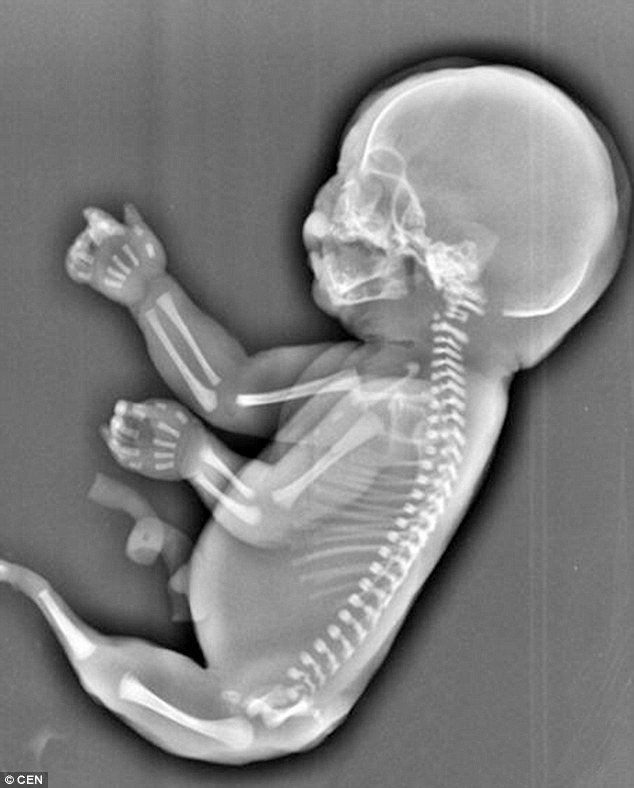

In cazul acestui sindrom rar, picioarele bebelusilor sunt unite, luand forma unei cozi de sirena, de unde si denumirea de sirenomelie.

Aceasta nu era singura problema cu care se confrunta bebelusul din pantecele chinezoicei. Fetusul nu avea vezica urinara, iar ficatul era atrofiat.

Medicii i-au spus tinerei ca, daca se va naste, copilul nu va supravietui mai mult de cateva ore din cauza problemelor de sanatate.

Medicina nu a putut determina care ar fi cauza aparitiei acestui sindrom, care afecteaza una din 100.000 de sarcini.